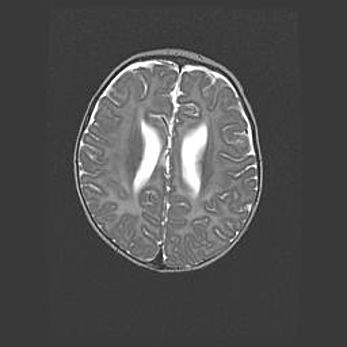

Церебральная ишемия II.

Возраст: 5 дней

Вес: 3400 г

Пол: женский

Окружность головы: 35 см

Срок гестации: 39 недель

Церебральная ишемия – это заболевание, характеризующееся недостаточностью (гипоксией) либо полным прекращением (аноксией) снабжения мозга кислородом по причине закупорки одного или нескольких сосудов. Это приводит к  что метаболическим расстройствам различной степени тяжести в тканях головного мозга, развитию коагуляционных некрозов и гибели нейронов.